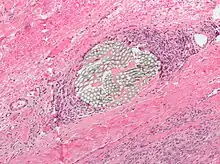

![]() Surgical suture and polypropylene thread held with a needle holder. Packaging shown above. |